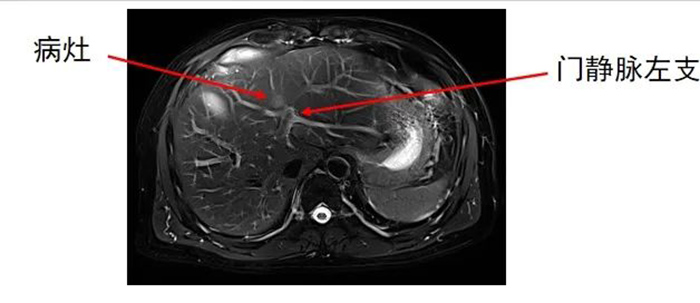

肝内转移灶数目为两个,分别位于左叶和右叶。

齐先生病灶临近大血管、重要脏器。厦门三院专家团队在CT引导下精准定位,经皮穿刺将微波消融针准确置入齐先生肝脏肿瘤部位,然后利用微波能量,使肿瘤组织内的水分子快速振动、摩擦产生热量,从而使局部温度迅速升高,让肿瘤细胞凝固性坏死。整个手术过程顺利,避免了严重并发症发生。

准确插入到病灶内,并避开了门静脉左支及分支,避免了出血并发症。